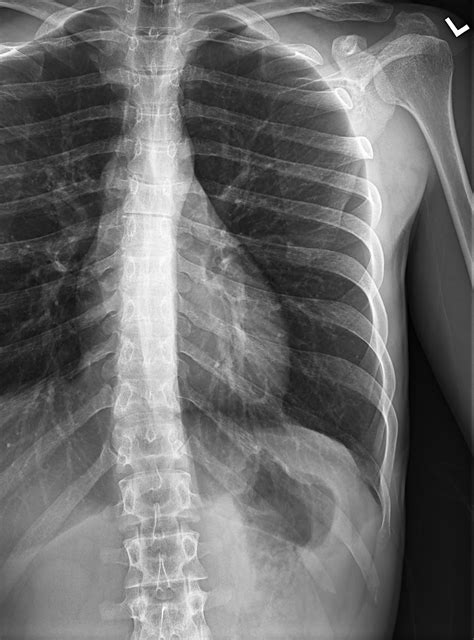

Swollen Ribs